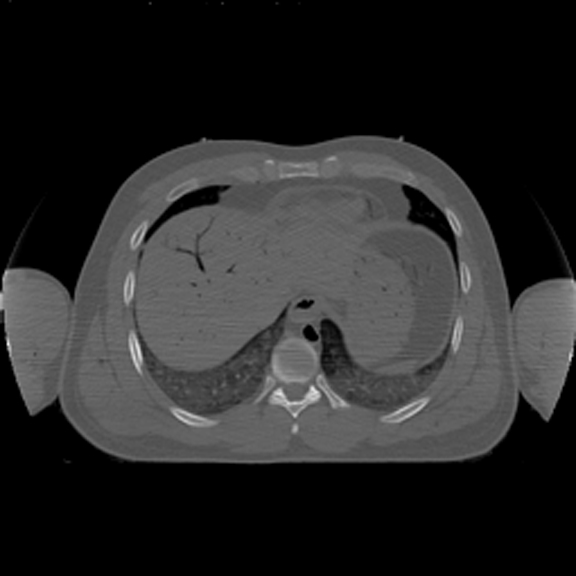

Horizontal CT Section at this level